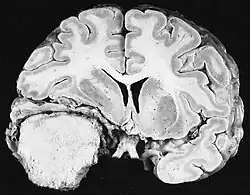

Cross section of a meningioma displacing the underlying brain.

Sources of ionizing radiation include medical imaging, and radon gas. Ionizing radiation is not a particularly strong mutagen.[87] Medical use of ionizing radiation is a growing source of radiation-induced cancers. Ionizing radiation may be used to treat other cancers, but this may, in some cases, induce a second form of cancer.[87] Radiation can cause cancer in most parts of the body, in all animals, and at any age, although radiation-induced solid tumors usually take 10–15 years, and can take up to 40 years, to become clinically manifest, and radiation-induced leukemias typically require 2–10 years to appear.[87] Radiation-induced meningiomas are an uncommon complication of cranial irradiation.[92] Some people, such as those with nevoid basal cell carcinoma syndrome or retinoblastoma, are more susceptible than average to developing cancer from radiation exposure.[87] Children and adolescents are twice as likely to develop radiation-induced leukemia as adults; radiation exposure before birth has ten times the effect.[87]